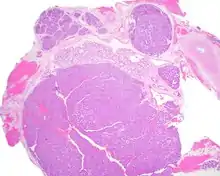

A hematoxylin and eosin stained slide of canalicular adenoma showing multifocality

Canalicular adenoma is most common in patients age 70 to 80, with females affected about four times as often as males. Most growths present in the upper lip; some also occur in the a few present in palate or buccal (cheek) tissue as a slowly enlarging mass.[3] The growths will often arise in multiple places at the same time or develop multiple nodes, despite not being clinically invasive or malignant.[1][4]